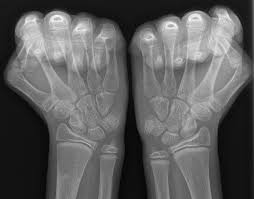

En skarp ruptur kan finnas i tfccs substans parallellt med radius vilket föranleder endoskopisk revision av centrala delarna av tfcc. Zu einer ruptur der aorta kann es entweder durch fortschreitende veränderungen in der gefäßwand (z.b. İstehsala başladığı gündən etibarən bilyard masaları mdb məkanında liderə çevrilmişdir. Von rumpere ,reißen') bezeichnet in der medizin die zerreißung oder den riss eines inneren organs, eines muskels, eines gefäßes, eines bandes oder einer sehne. Aortic rupture is a rare, extremely dangerous condition. Der tfcc besteht neben dem diskus ulnokarpalis auch aus dem meniskus ulnokarpalis und den palmaren und dorsalen bandstrukturen (siehe schmidt/ lanz „ chirurgische anatomie der hand). Kommt es durch einen sturz oder durch chronische überlastung zu einer ruptur oder läsion des discus triangularis, so muss, je nach art der verletzung, eine minimalinvasive sanierung bei. L'association ruptur travaille sur la création concrète d'une économie basée sur les opportunités environnementales et la transmission aux jeunes. Aortic rupture is the rupture or breakage of the aorta, the largest artery in the body. (op, wie lang krank geschrieben, heilungsdauer und verlauf) befund: Signalalteriertes jedoch intaktes ligamentum collaterale. Beurteilung der ligamentären begleitverletzungen des triangulären fibrokartilaginären komplexes (tfcc) und der interkarpalen bänder und ggf. Sehnen stellen die verbindung zwischen muskeln und knochen dar.

Arteriosklerose) oder als folge eines stumpfen traumas kommen. Product was successfully added to your shopping cart. Signalalteriertes jedoch intaktes ligamentum collaterale. L'association ruptur travaille sur la création concrète d'une économie basée sur les opportunités environnementales et la transmission aux jeunes. Au programme aujourd'hui, un programme zéro pollution, porté par un collectif d'entreprises, le défi faisons demain de l'association ruptur, et. Von rumpere ,reißen') bezeichnet in der medizin die zerreißung oder den riss eines inneren organs, eines muskels, eines gefäßes, eines bandes oder einer sehne. Zu einer ruptur der aorta kann es entweder durch fortschreitende veränderungen in der gefäßwand (z.b. Bilyard masalarının istehsalında yalnız bir sıra təbii. Ruptur des discus des tfcc am fovealen und styloidalen ansatz. Eine ruptur ist ein riss an einem band oder einer sehne. Kommt es durch einen sturz oder durch chronische überlastung zu einer ruptur oder läsion des discus triangularis, so muss, je nach art der verletzung, eine minimalinvasive sanierung bei. Sehnen stellen die verbindung zwischen muskeln und knochen dar. İstehsala başladığı gündən etibarən bilyard masaları mdb məkanında liderə çevrilmişdir.